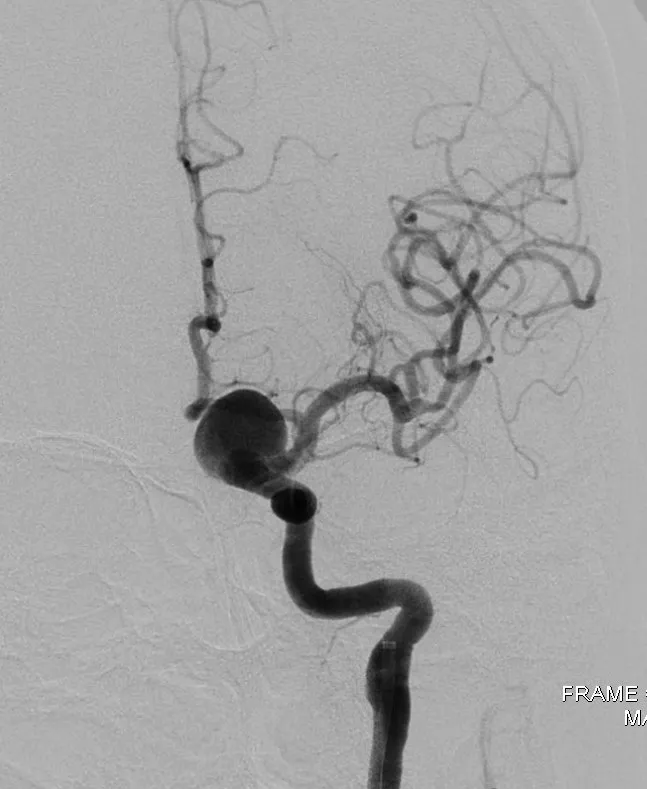

Theo TS-BS Phú, một tuần trước, bệnh nhân V nhập viện trong tình trạng nhức đầu dữ dội và huyết áp cao. Tiền sử cao huyết áp và nhức đầu thường xuyên. Qua thăm khám và kết quả hình ảnh chụp cắt lớp, các BS chẩn đoán bệnh nhân bị túi phình lớn động mạch cảnh trong bên trái ở não. Ngay lập tức, BV đã tổ chức hội chẩn và nhanh chóng can thiệp cho bệnh nhân bằng phương pháp mới, đó là đặt một stent thay đổi dòng chảy ngang qua túi phình, qua đó túi phình dần dần co nhỏ và tắc.

Thủ thuật thực hiện trên máy DSA hiện đại với những chức năng giúp BS dễ dàng giúp đặt stent đúng vị trí như mong muốn”, TS-BS Phú nói.

Cũng theo TS Phú, phương pháp đặt một stent ngang qua cổ làm thay đổi dòng chảy, hạn chế dòng chảy qua túi phình là một đột phá trong điều trị đối với các túi phình có kích thước lớn, phình dạng hình thoi mà trước đây các phương pháp can thiệp khác vẫn còn nhiều hạn chế và qua đó góp phần điều trị triệt để các tổn thương phức tạp này, cứu sống người bệnh thoát khỏi tử vong trong gang tấc và những hậu quả nghiêm trọng mà nó gây ra. Chi phí thấp hơn so với các phương pháp kinh điển.